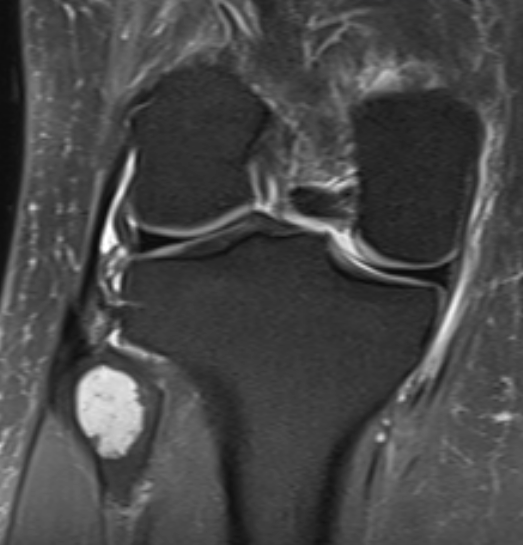

3. Enchondroma of fibula head